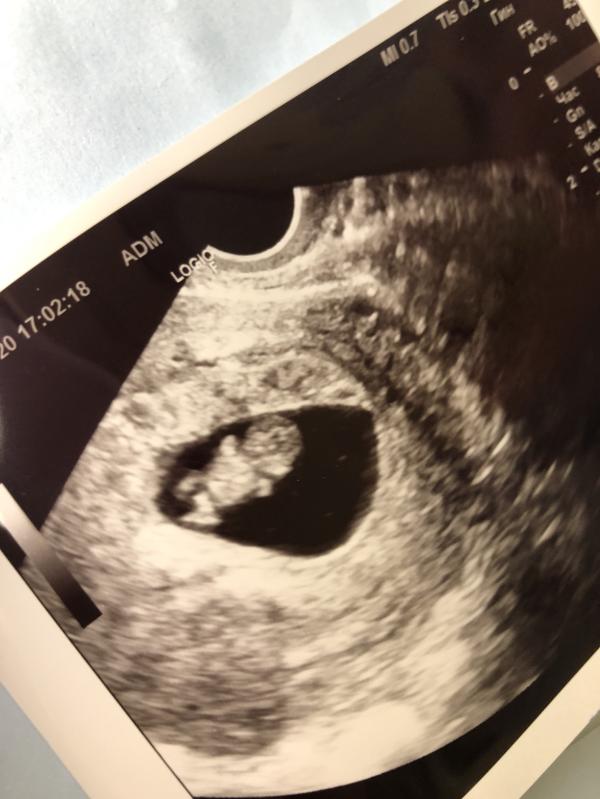

На фото срок 9.1, а вот по размерам 9,4, интересно, это значит что малыш большой растёт?)

С размером, может так посчитали. Бывает. Но мне говорили +-4 дня это в срок идёт значит.

Просто странно так) мне делали узи на 7 неделе, там даже эмбрион не визуализировался, а теперь даже больше чем по сроку😂

У меня было расхождение на 2,5-3 недели!))) даже с планового кс отправили еще недельку гулять. родился оч большой и до сих пор выше всех. Три дня это не расхождение, все нормально, не переживайте!